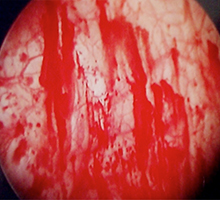

わが国では、ハンナ病変(正常の毛細血管構造を欠く特有の発赤粘膜)または膀胱水圧拡張後の点状出血の確認が重要視されています。

- 膀胱内にハンナ病変または膀胱拡張術後の点状出血を認める。